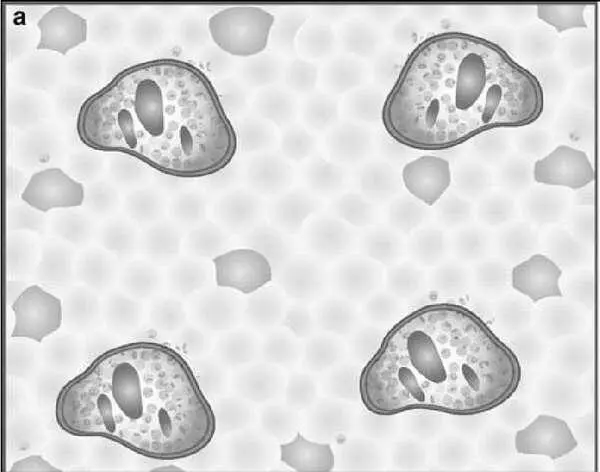

Разработчики ставили цель упростить шкалу. Оригинальность подхода заключается в том, что шкала представлена в виде 4 диаграмм, оценивающих некротические и воспалительные изменения в биоптате печени, и 4 диаграмм, оценивающих стадию фиброза .

Рисунок 5 – Схемы некротических и воспалительных изменений в печени (по Batts KP, Ludwig J.)

На рисунке представлена последовательная схема некротических и воспалительных изменений в печени при хроническом гепатите (по Batts–Ludwig). Воспалительная инфильтрация портальных трактов является обязательным компонентом поражения печени при гепатите и оценивается во всех системах. В оценочной шкале Баттс–Людвига выраженность гистологической активности гепатита градируется от 1 до 3 (a, b, c). На рисунке d представлена схема сливных некрозов в виде мостовидных некрозов, которые свидетельствуют о выраженной степени активности гепатита и соответствуют 4 стадии активности по системе Баттс–Людвига (Batts KP, Ludwig J. Chronic hepatitis. An update on terminology and reporting. Am J Surg Pathol 1995;19:1409–1417.15).